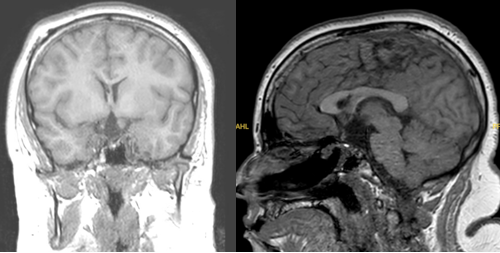

一位14岁患儿因视力模糊和剧烈头痛就诊,检查发现一个位于视交叉后方、伴有钙化的颅咽管瘤。主刀医生Rutka教授首先为患儿进行了脑室-腹腔分流术,缓解脑积水;随后通过内镜经鼻入路完成肿瘤全切。术后患儿视力显著改善,开始接受激素替代治疗,至今未见复发。

术后